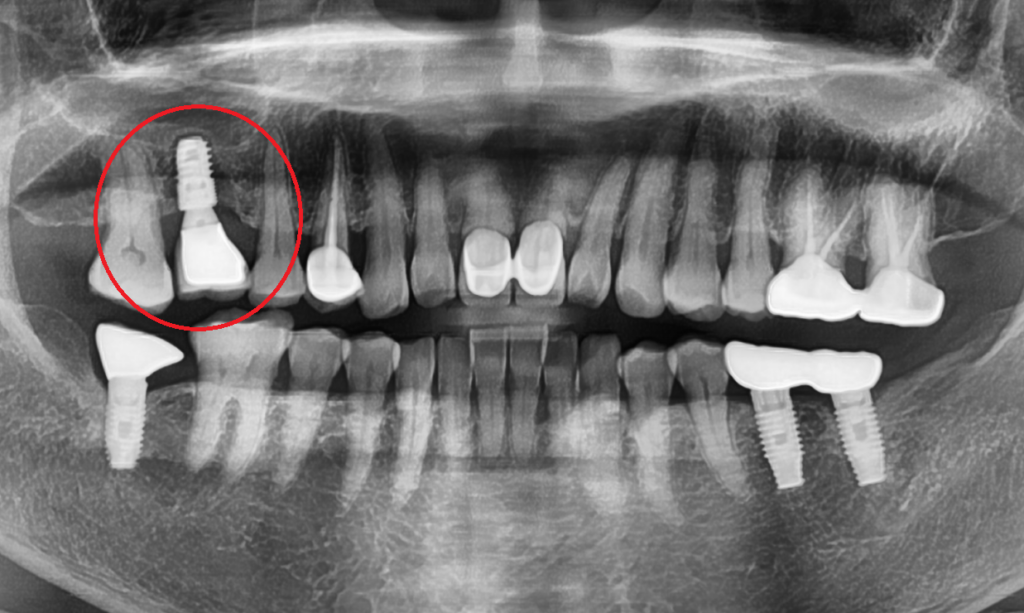

23. 10. 25(임플란트 식립 후 확인 x-ray)

대합되는 치아에 온전한 힘을 받을 수 있도록 임플란트를 제 위치에 식립해드렸고, 협측부의 소실된 부위에도 뼈이식을 동반하여 ,골조직 재건을 형성 하였습니다.

23.10.25(CT상 임플란트 재수술 후 골유착이 일어난 모습)

CT상 임플란트 재수술 후 골유착이 일어난 모습 이렇게 치료를 마치고, 임플란트 치아의 머리까지 완성해 드렸습니다.